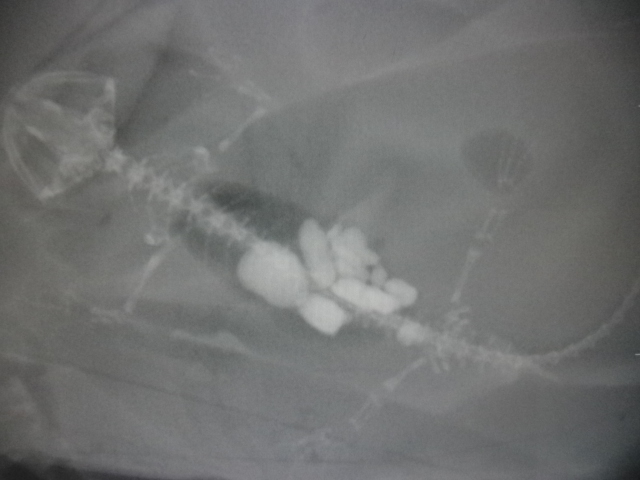

この子はX線写真の通り、底石を複数誤食してしまい食欲が低下していました。

細かい砂だったり、少量の誤食だった場合には吐き戻したり、便と一緒に排出できたりしますが、このくらい入ってしまうと難しくなってきます。

治療は開腹手術による異物摘出となります。